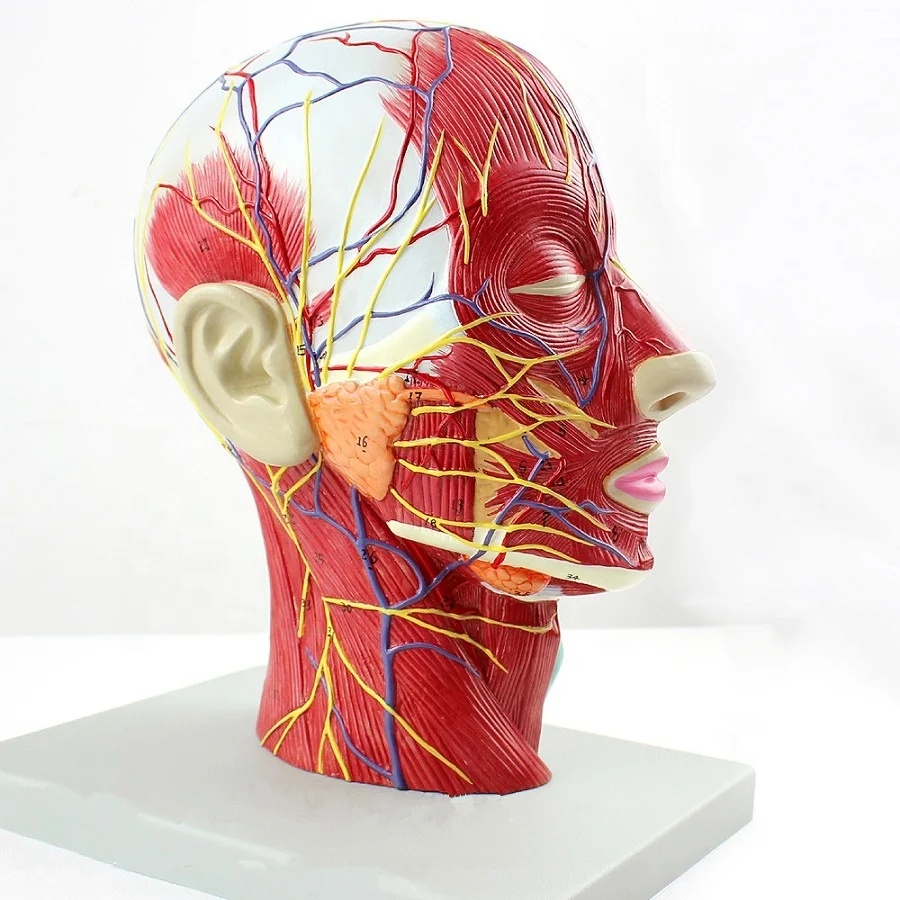

2. Anatomically mimic muscular system with the main superficial arteries, veins and nerves and the area of the neck are demonstrated.

3. 100 positions are displayed.

Size:life size 27*10*20cm